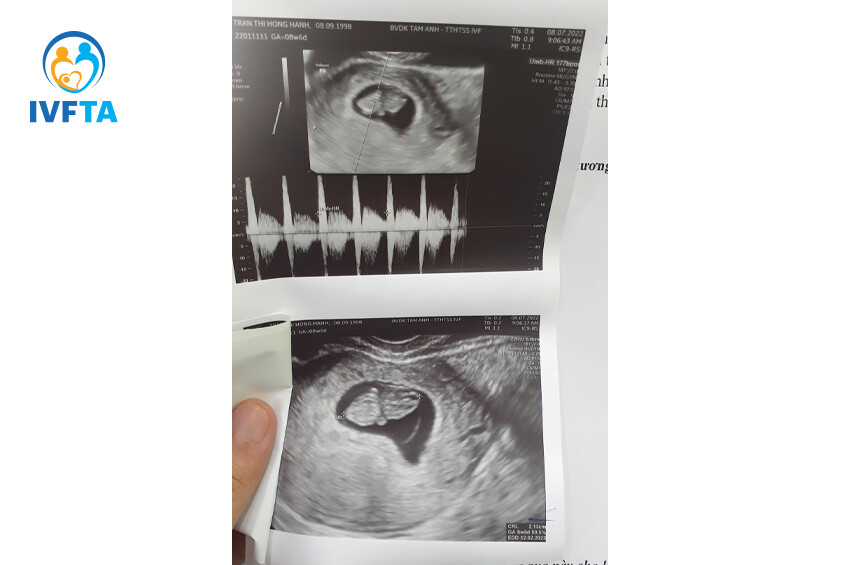

Khoảnh khắc đáng nhớ nhất là khi tôi nhận được kết quả beta hCG. Con số nhỏ trên tờ giấy khiến tôi òa khóc, đó là những giọt nước mắt của sự hạnh phúc và biết ơn. Cả hành lang bệnh viện như mờ đi trong giây phút ấy. Tôi đã mang thai, sau bao ngày tháng chờ đợi!

Hành trình mang thai cũng có những lúc lo lắng, nhất là với một thai kỳ quý giá. Nhưng mọi điều tôi cần là sự yên tâm thì tại IVF Tâm Anh, tôi luôn có đủ. Các bác sĩ theo sát thai kỳ của tôi, tư vấn từng mốc khám thai, động viên và sẵn sàng hỗ trợ bất cứ lúc nào tôi có thắc mắc. Không phải một ai đó nổi bật riêng biệt, mà chính cả tập thể ấy, những người âm thầm đứng sau quá trình điều trị đã chạm vào trái tim tôi.